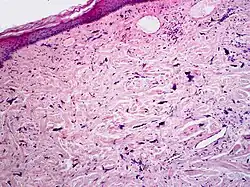

Pleomorphic fibroma

Pleomorphic fibromas of the skin usually present in adults, with a slight preponderance in women.[1]